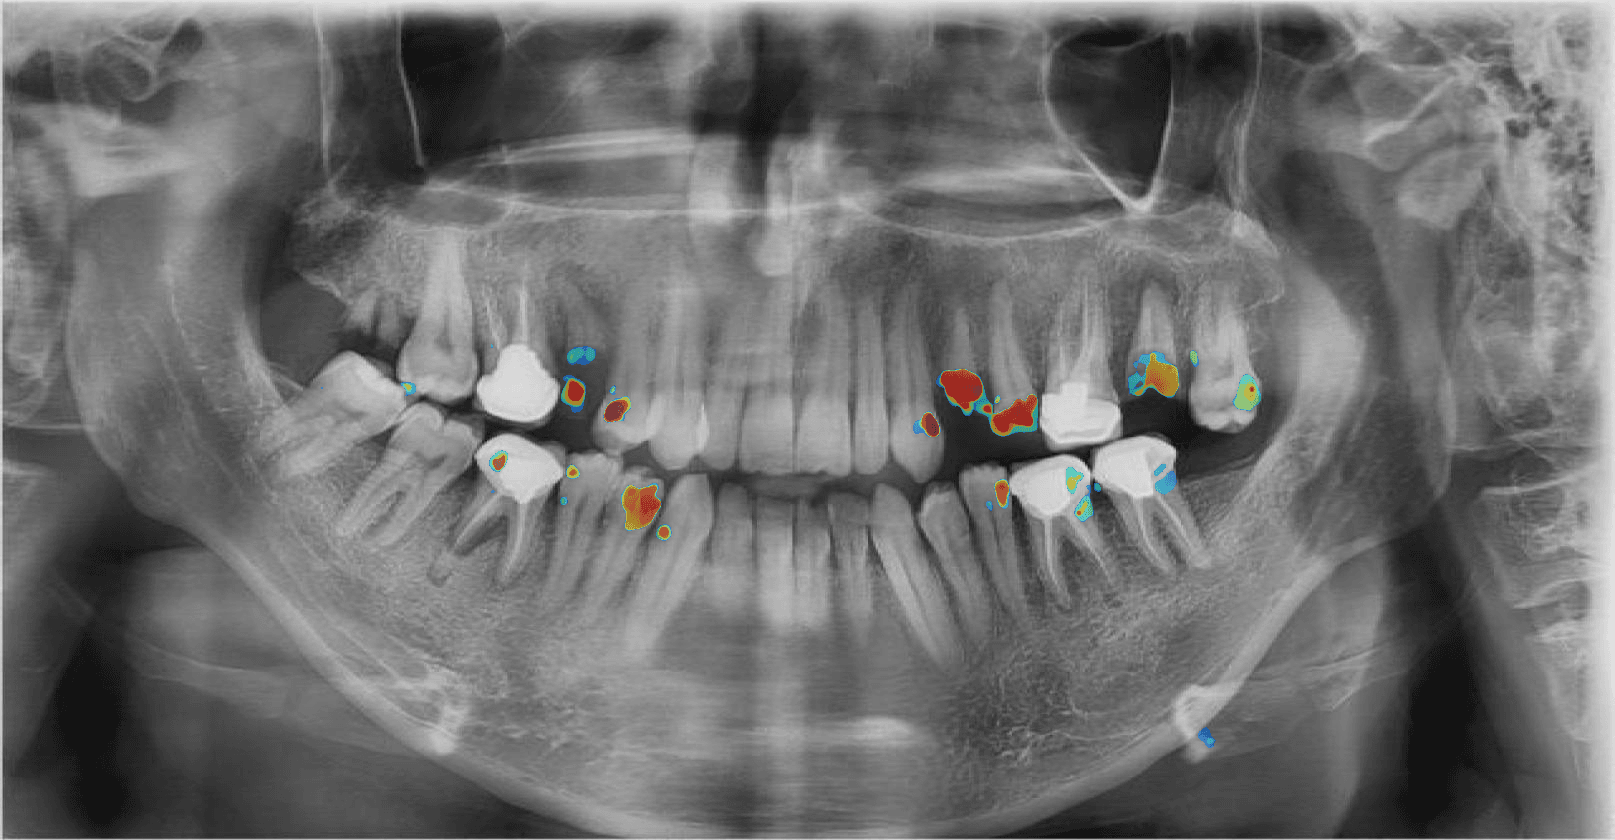

3. Diagnóstico Visual

Receba um dashboard interativo com heatmaps, níveis de confiança e sugestões de tratamento para validar.

Detecção de Cáries

Identificação precisa de lesões cariosas iniciais e avançadas com classificação de severidade.

Score de Confiança

Cada achado clínico acompanha um percentual de confiança da IA (Confidence Score) para apoiar sua decisão.